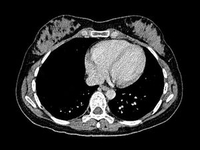

一项新研究显示,对于在过去90天接受手术的急性卒中患者,对其行溶栓治疗,其手术区域总体出血发生率低。德国慕尼黑Nicolas Voelkel, Städtisches Klinikum在最近举行的首届欧洲卒中组织(ESO)会议中提到2015年的数据,他说,这是第一次探讨研究围手术期的溶栓治疗,“这些结果表明,tPA(组织型纤溶酶原激活剂)可以安全的应用于最近行手术治疗的患者。”

[ESOC2015]越来越多的证据支持为极重度卒中患者进行溶栓

一项大型脑卒中溶栓国际注册登记研究的新数据显示,组织型纤溶酶原激活物(tPA,阿替普酶)可安全用于极重度脑卒中患者的溶栓治疗。该研究的主要作者、来自瑞典斯德哥尔摩市Karolinska学院的Michael Mazya博士,已经在新近举行的2015年欧洲脑卒中组织(ESO)大会上报告了其上述的研究结果。